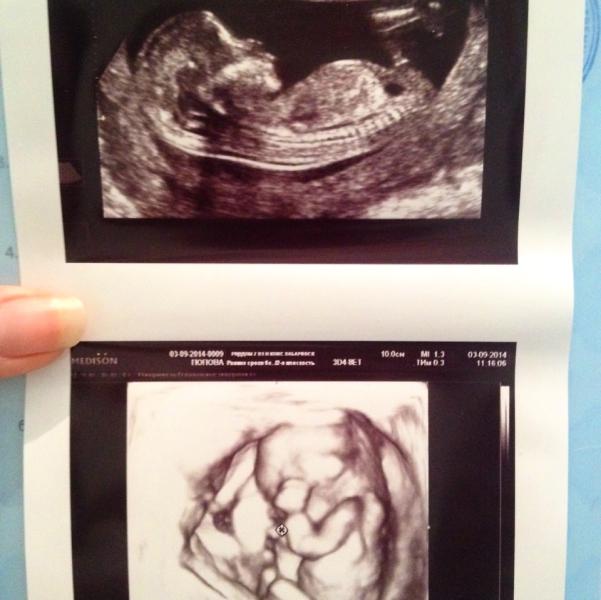

Вот и я наконец то сходила на свое первое УЗИ!!!😊🎉🎉 срок все таки 13 недель и 4 дня, серцебиение 148 уд/мин., все конечности и органы на месте, сказали что мой малыш здоровый как бык‼️ фото стоило 237 рублей😔 но вторую дали бесплатно за то что показал все что нужно, хоть и в самом начале скрестил ножки и сосал пальчик))) и кстати на счет пола малыша, сначала сказали на девчушку похоже, но через несколько секунд нам сказали что между ножек что -то похожее на писюн))) так что пока не понятно 😊😊😊 во...